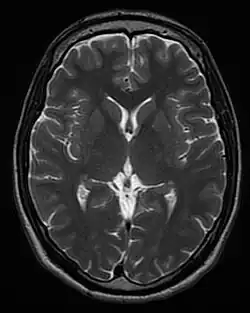

Each tissue returns to its equilibrium state after excitation by the independent relaxation processes of T1 (spin-lattice; that is, magnetization in the same direction as the static magnetic field) and T2 (spin-spin; transverse to the static magnetic field). To create a T1-weighted image, magnetization is allowed to recover before measuring the MR signal by changing the repetition time (TR). This image weighting is useful for assessing the cerebral cortex, identifying fatty tissue, characterizing focal liver lesions, and in general, obtaining morphological information, as well as for post-contrast imaging. To create a T2-weighted image, magnetization is allowed to decay before measuring the MR signal by changing the echo time (TE). This image weighting is useful for detecting edema and inflammation, revealing white matter lesions, and assessing zonal anatomy in the prostate and uterus.

MRI is the investigative tool of choice for neurological cancers over CT, as it offers better visualization of the posterior cranial fossa, containing the brainstem and the cerebellum. The contrast provided between grey and white matter makes MRI the best choice for many conditions of the central nervous system, including demyelinating diseases, dementia, cerebrovascular disease, infectious diseases, Alzheimer's disease and epilepsy.[22][23][24] Since many images are taken milliseconds apart, it shows how the brain responds to different stimuli, enabling researchers to study both the functional and structural brain abnormalities in psychological disorders.[25] MRI also is used in guided stereotactic surgery and radiosurgery for treatment of intracranial tumors, arteriovenous malformations, and other surgically treatable conditions using a device known as the N-localizer.[26][27][28] New Artificial intelligence in healthcare tools have demonstrated higher image quality and morphometric analysis in neuroimaging with the application of a denoising system.[29]